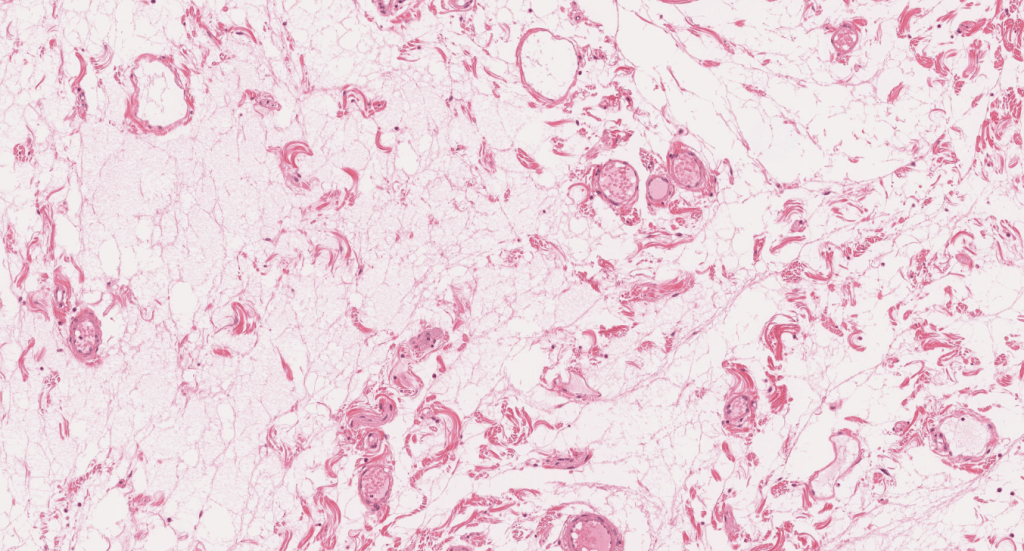

TEJIDO CONJUNTIVO LAXO (TCL)

Se ubica por en la Dermis papilar, debajo de los epitelios (Lámina Propia), alrededor de los vasos, contiene muchas células y pocas fibras.

También llamado TC areolar.